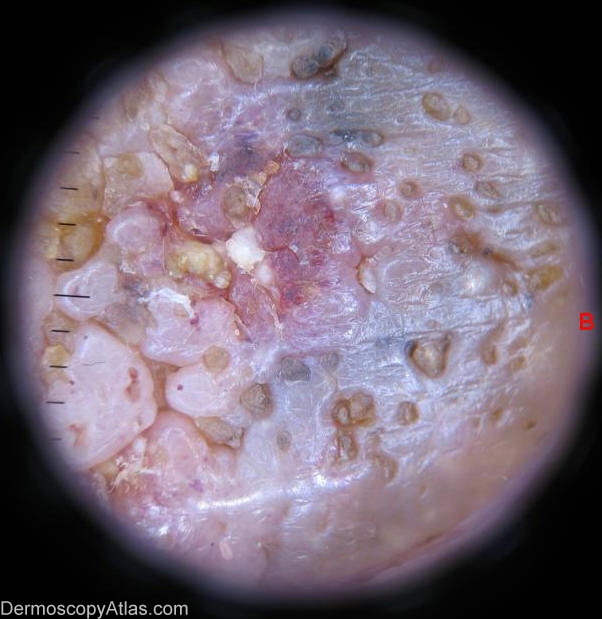

Image Number #2234 (Seborrhoeic keratosis)

Site: Breast

Diagnosis: Seborrhoeic keratosis

Sex: F

Age: 73

Type: Dermlite Non Polarised

73 year old lady with recent change in colouration of her mole on her left breast.She had total mastectomy for her right breast carcinoma done over twenty years ago.